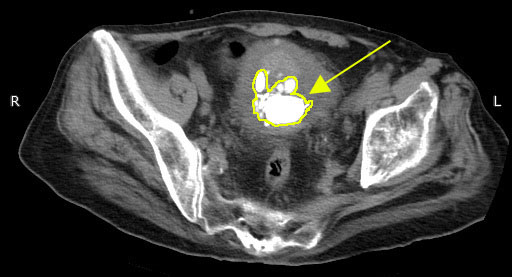

膀胱結石のCT

※膀胱結石のCT画像